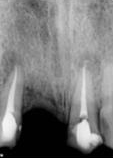

antes depois